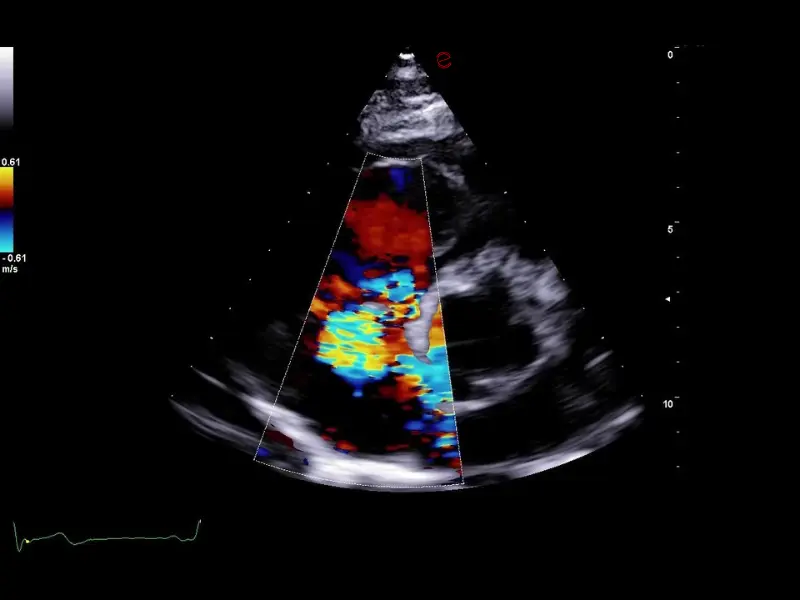

MyLab™C30 - CFM - TR

MyLab™C30 - CFM - TR